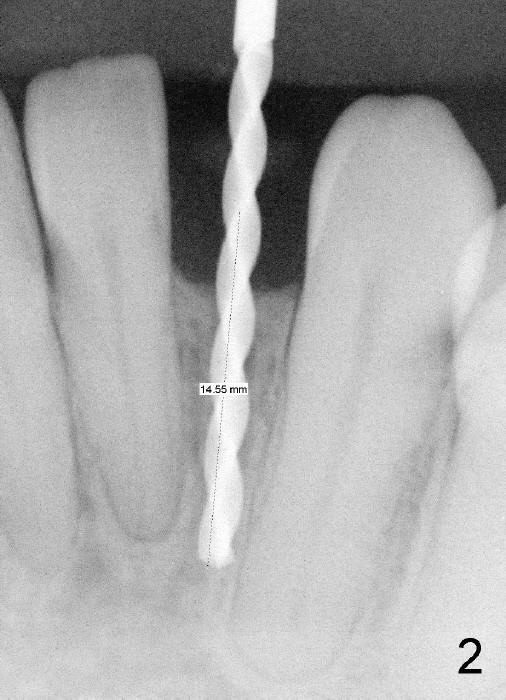

Informed consent is obtained with emphasis of potential damage to the neighboring roots.  Two PAs have to be taken with the first pilot drill (1.5 mm) in place for determination of initial trajectory (Fig.2,3).  Osteotomy is enlarged coronally with 2 mm pilot drill.  Finally a 3x17 mm one piece implant is placed with primary stability, determined tactilely (Fig.4).  Immediate provisional is fabricated.  To avoid micromovement, the immediate provisional (Fig.5 P) is bonded to the neighboring teeth with composite (*); it is further fixed in place with a lingual retainer (Fig.6 arrowhead).